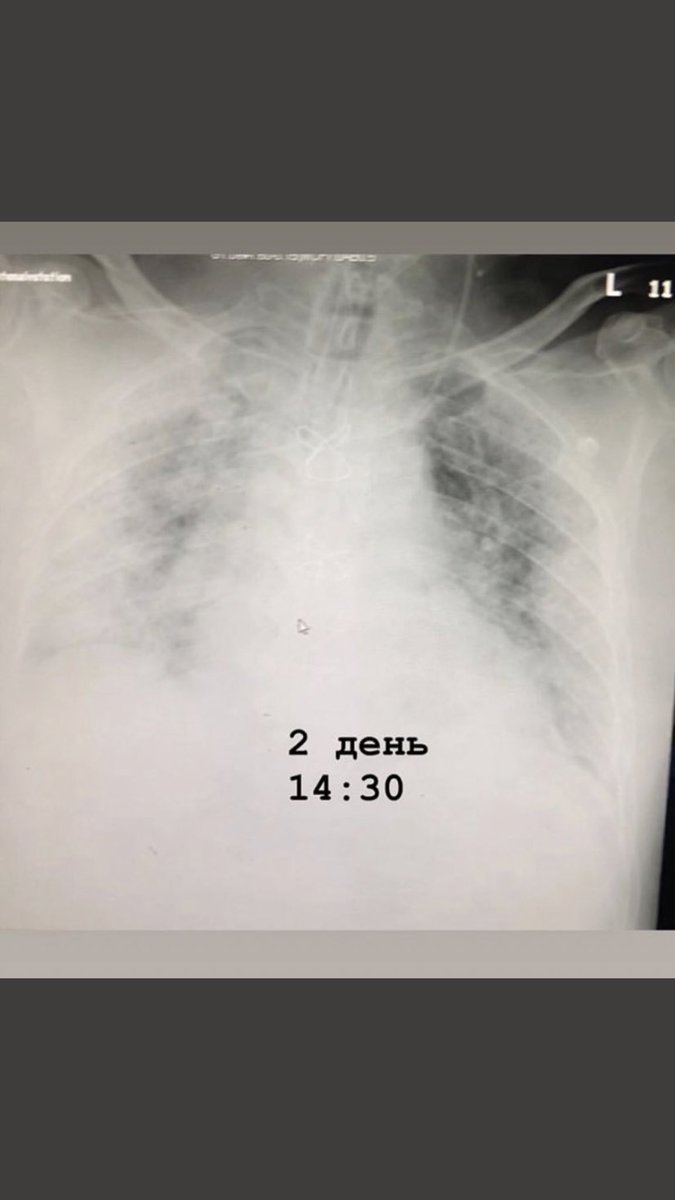

Поражение Легких При Коронавирусе Фото Рентгена

Поражение Легких При Коронавирусе Фото Рентгена 111 фото